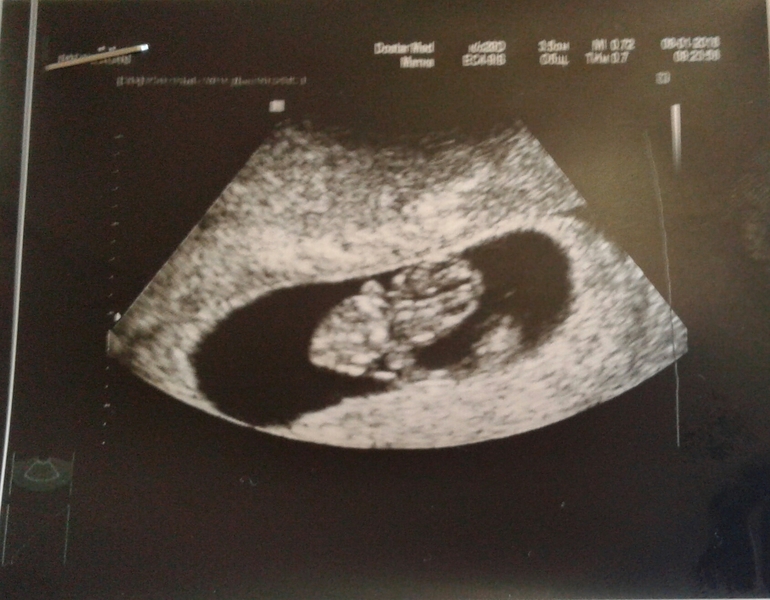

а вот и наш малыш:

УЗИ, КТГ, доплерСходила сегодня к своему врачу.должна была в пон.но пошла по раньше т.к. муж был дома и мог отвезти) в общем переживания мои были напрасны. Малыш уже 21 мм. Дали послушать сб... правда узист другой был и поставил что гематома 2 см хотя до этого 10 дней назад ставили 8мм. Но гинеколог говорит это не факт что она растет т.к. каждый узист измеряет по разному.оставили дюфастон 3 раза в день.эмбриональные недели поставили 7-8)